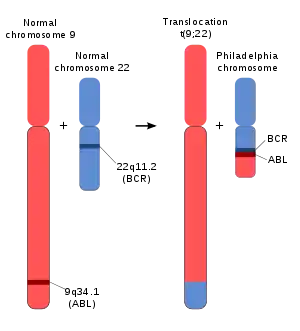

The Philadelphia chromosome or Philadelphia translocation (Ph) is a specific genetic abnormality in chromosome 22 of leukemia cancer cells (particularly chronic myeloid leukemia (CML) cells). This chromosome is defective and unusually short because of reciprocal translocation, t(9;22)(q34;q11), of genetic material between chromosome 9 and chromosome 22, and contains a fusion gene called BCR-ABL1. This gene is the ABL1 gene of chromosome 9 juxtaposed onto the breakpoint cluster region BCR gene of chromosome 22, coding for a hybrid protein: a tyrosine kinase signaling protein that is "always on", causing the cell to divide uncontrollably by interrupting the stability of the genome and impairing various signaling pathways governing the cell cycle.[1]

The chromosomal defect in the Philadelphia chromosome is a reciprocal translocation, in which parts of two chromosomes, 9 and 22, swap places. The result is that a fusion gene is created by juxtaposing the ABL1 gene on chromosome 9 (region q34) to a part of the BCR (breakpoint cluster region) gene on chromosome 22 (region q11). This is a reciprocal translocation, creating an elongated chromosome 9 (termed a derivative chromosome, or der 9), and a truncated chromosome 22 (the Philadelphia chromosome, 22q-).[5][6] In agreement with the International System for Human Cytogenetic Nomenclature (ISCN), this chromosomal translocation is designated as t(9;22)(q34;q11). The symbol ABL1 is derived from Abelson, the name of a leukemia virus which carries a similar protein. The symbol BCR is derived from breakpoint cluster region, a gene which encodes a protein that acts as a guanine nucleotide exchange factor for Rho GTPase proteins.[7]

The Philadelphia chromosome is designated Ph (or Ph') chromosome and designates the shortened chromosome 22 which encodes the BCR-ABL fusion gene/protein kinase. It arises from the translocation, which is termed t(9;22)(q34.1;q11.2), between chromosome 9 and chromosome 22, with breaks happening in region (3), band (4), sub-band (1) of the long arm (q) of chromosome 9 and region (1), band (1), sub-band (2) of the long arm (q) of chromosome 22. Hence the chromosome breakpoints are written as (9q34.1) and (22q11.2), respectively, using ISCN standards.